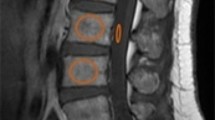

At the time of enrollment and at the 3- and 6-month follow-ups, the patients were examined using plain radiography and spine MRI. MRI was carried out with 1.5-T MRI scanners. The multifidus (MF) and erector spinae (ES) including the longissimus and iliocostalis were identified as the medial-to-lateral PVMs. The border between the MF and ES was scouted from the mammillary processes [20]. The cross-sectional area (CSA) was calculated by the average of the left and right PVM regions of interest of the axial T2-weighted image. The fat signal fraction (FSF) was calculated as the ratio of signal fat/CSA × 100. The CSA and FSF at the superior endplate of L3 were measured using a software program (Horos, version 2.0.1, Horos Project). PVM decrease was defined as > 1 standard deviation (SD) decrease in the CSA (0.9 cm2) or > 1 SD increase in the FSF (5.7%) at the 6-month follow-up compared with the values at the time of injury.

Plain radiographs were assessed on the sagittal view in both the supine and weight-bearing positions. The relative height of the anterior wall (%) was calculated by the following formula: [2 × affected vertebral height / (lower vertebral height + upper vertebral height)] × 100 [18]. When either the cranial or caudal adjacent vertebral body was deformed due to an old fracture, the vertical height of the anterior wall of the fractured vertebral body was divided by the vertical height of the anterior wall of the undeformed adjacent vertebral body. Delayed union was defined by a recognizable intravertebral cleft on plain radiography at the 6-month follow-up. Dual-energy x-ray absorptiometry was used to measure the bone mineral density (BMD) of the mean femoral neck at the time of enrollment.

Regarding the trend of the CSA and FSF, there were no trends in the CSA of ES, MF, and total PVM (Table 1). On the other hand, the FSF in both ES and MF showed an increasing tendency from 42.3% ± 7.8% and 53.0% ± 8.9% to 44.2% ± 8.3% and 55.4% ± 9.3%, respectively, for 6 months (p = 0.078 and 0.055, respectively). The FSF of total PVM showed a significant increase from 47.7 to 49.8% for the period (p = 0.033). The mean change in the CSA and FSF of total PVM was − 0.2 cm2 ± 0.6 cm2 and 2.1% ± 3.6%, respectively. There were 30 patients with PVM decrease at the 6-month follow-up.

The results of the multivariate logistic regression model are listed in Table 5. Compared with the status of “dependent or requires assistance to leave home,” patients with the status of “bedridden or nearly bedridden” at the 3-month follow-up displayed a fourfold increase of the risk for PVM decrease (OR = 5.35; 95% CI, 1.23–23.34). Patients who had delayed union at 6-month follow-up also increased the OR for PVM decrease (OR = 4.12; 95% CI, 1.16–14.71). The admission significantly reduced the risk for PVM decrease (OR = 0.24; 95% CI, 0.06–0.97). VAS of back pain at the 6-month follow-up was associated with PVM decrease (OR = 1.24; 95% CI, 1.02–1.49). A typical case was shown in supplementary figure. The case showed the increase of the FSF at 3- and 6-month follow-up.